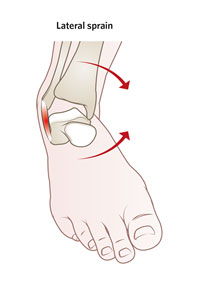

足踝扭傷,俗稱「拗柴」,是最常見的足踝關節疾病之一。足踝扭傷(拗柴)是因為內翻或外翻扭傷而導致韌帶撕裂,通常會伴隨疼痛、腫脹甚至行走困難。常見的足踝扭傷(拗柴)情況,例如在不平坦的路面上行走或跑步、走路時踩空或者穿著不合適的鞋子(例如: 高跟鞋),都很容易導致踝關節內翻或外翻扭傷,通常是內翻扭傷(±95% ),外翻扭傷較少 (±5%)

| 足踝內翻扭傷 |

外側翻踝腫痛 |